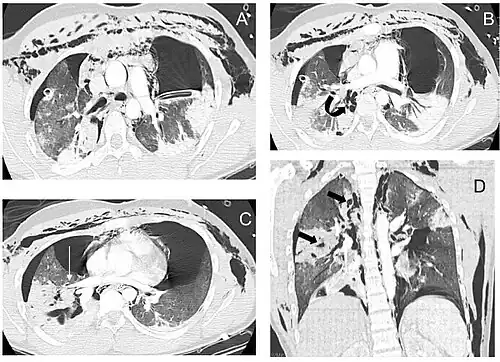

La radiografía de tórax es la técnica de imagen inicial usada para diagnosticar la LCT.[17] La radiografía puede no tener ningún signo en un paciente por lo demás asintomático.[15] Las indicaciones de LCT vistas en las radiografías incluyen deformidad en la tráquea o un defecto en la pared traqueal.[17] La radiografía también puede mostrar enfisema cervical, aire en los tejidos del cuello.[2] Las radiografías también pueden mostrar lesiones y signos acompañantes como fracturas y enfisema subcutáneo.[2] Si se produce un enfisema subcutáneo y el hueso hioides aparece en una radiografía a una altura inusual en la garganta, puede ser un indicio de que la tráquea ha sido seccionada.[4] También se sospecha de LCT si un tubo endotraqueal aparece en una radiografía fuera de lugar, o si su manguito parece estar más lleno de lo normal o sobresale a través de un desgarro en las vías respiratorias.[17] Si se desgarra un bronquio en toda su extensión, el pulmón puede colapsarse hacia fuera, hacia la pared torácica (en lugar de hacia dentro, como suele ocurrir en el neumotórax), porque pierde la unión al bronquio que normalmente lo mantiene hacia el centro.[6] En una persona tumbada boca arriba, el pulmón se colapsa hacia el diafragma y la espalda.[23] Este signo, descrito en 1969, se denomina signo del pulmón caído y es patognomónico de LCT (es decir, es diagnóstico de LCT porque no se produce en otras afecciones); sin embargo, sólo se produce en raras ocasiones.[6] Hasta en uno de cada cinco casos, las personas con traumatismo contuso y LCT no presentan signos de la lesión en la radiografía de tórax.[23] La TC detecta más del 90% de los TLC resultantes de traumatismo contuso,[3] pero ni la radiografía ni la TC sustituyen a la broncoscopia.[6]